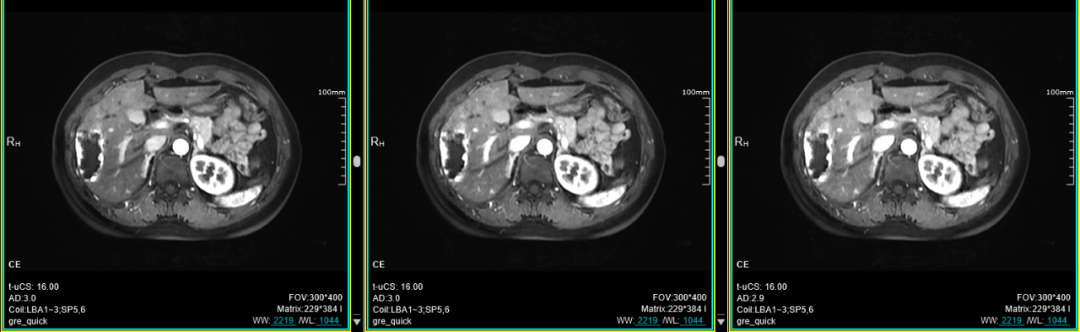

十、肝脏动脉期多期扫描技术(最多可达32期):此项检查技术主要应用于上腹部,尤其是应用于不同期相肝脏富血供肿瘤的检出上。

联影磁共振怎么样平原县第一人民医院联影uMR780 光梭3.0T磁共振正式投入使用,开启医学影像新时代!_https://www.jmylbn.com_新闻资讯_第27张

联影磁共振怎么样平原县第一人民医院联影uMR780 光梭3.0T磁共振正式投入使用,开启医学影像新时代!_https://www.jmylbn.com_新闻资讯_第28张